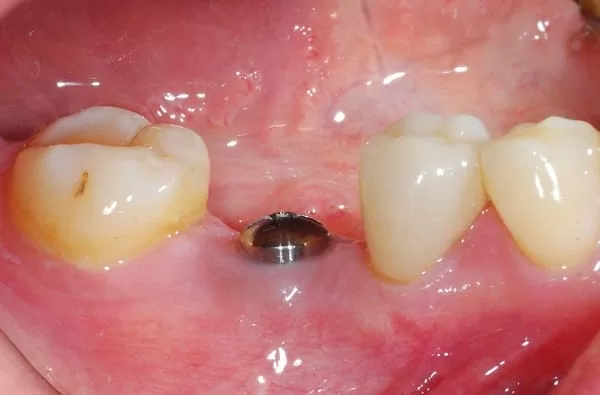

所以等約四個月後植牙,再等待三個月以新科技的植牙穩定度測量儀測量骨整合程度,發現骨整合情況良好,隨即以"臨時牙套"進行牙齦塑型,再製作全瓷冠恢復我的咀嚼功能。

經牙嵴保存術後再植牙,醫師說:這就是"植牙癒合帽"周圍牙嵴豐隆度很好~ (# ̄▽ ̄#)